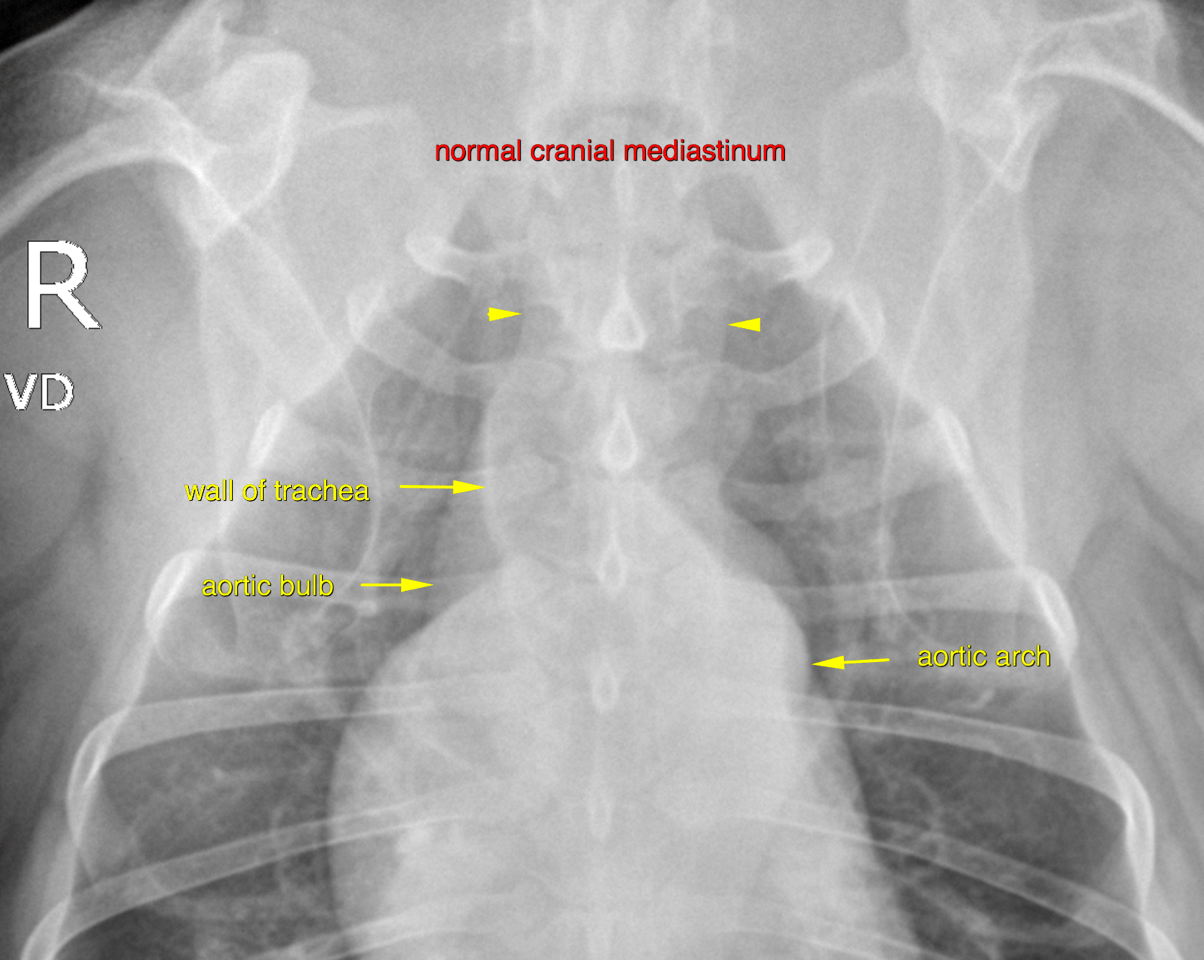

The patient is a 9 year old FS Pitbull with a 3 day history of lethargy and decreased appetite. Has not eaten in 24 hours, decreased water intake. Seems almost ataxic or weak to the owner at home, overall very depressed. Hx of allergies that are controlled.

Physical Exam: Depressed, Temp 101.9. MM pink/slightly tacky. cardiac wnl, lungs wnl on auscultation. BCS 5/9. No abdominal discomfort on palpation. Walking normally x 4 in room but is much less energetic than usual.